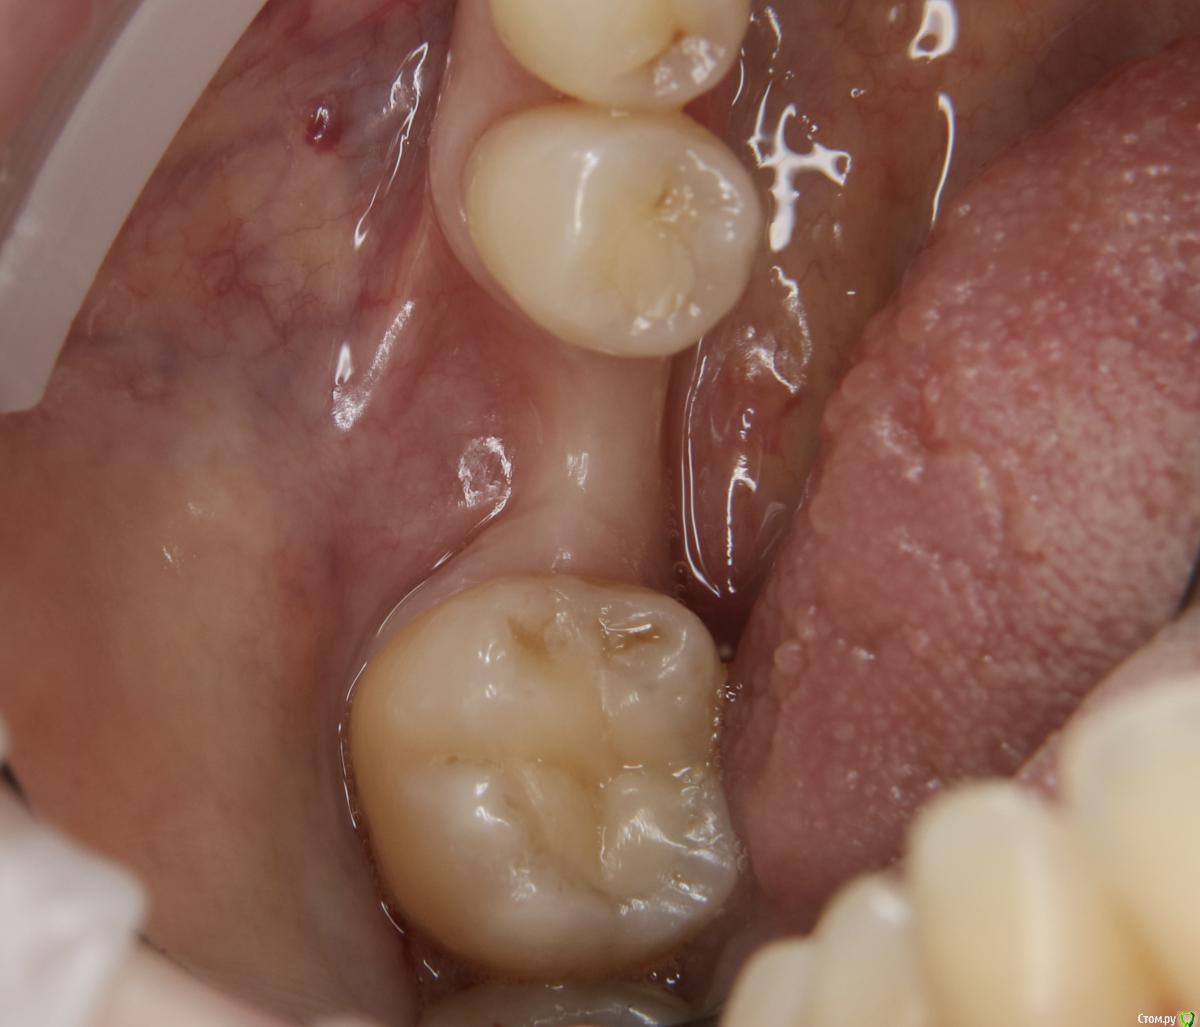

Александр07 Опубликовано 21 августа, 2020 Поделиться Опубликовано 21 августа, 2020 Коллеги добрый день, решил углубиться в тематику костных пластин по Кюри, определенные знания и некоторый опыт есть, небольшой, хотел поделиться последней работой, если какие то советы /замечания есть с удовольствием выслушаю 8 Ссылка на комментарий